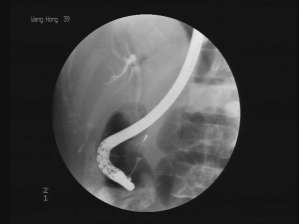

熊建光:ERCP即内镜下逆行胰胆管造影,是将十二指肠镜插至十二指肠降段,找到十二指肠乳头,经内镜活检孔道插入一造影导管,由乳头开口部,进入胆管或胰管内,注入造影剂,作X线胰胆管造影。